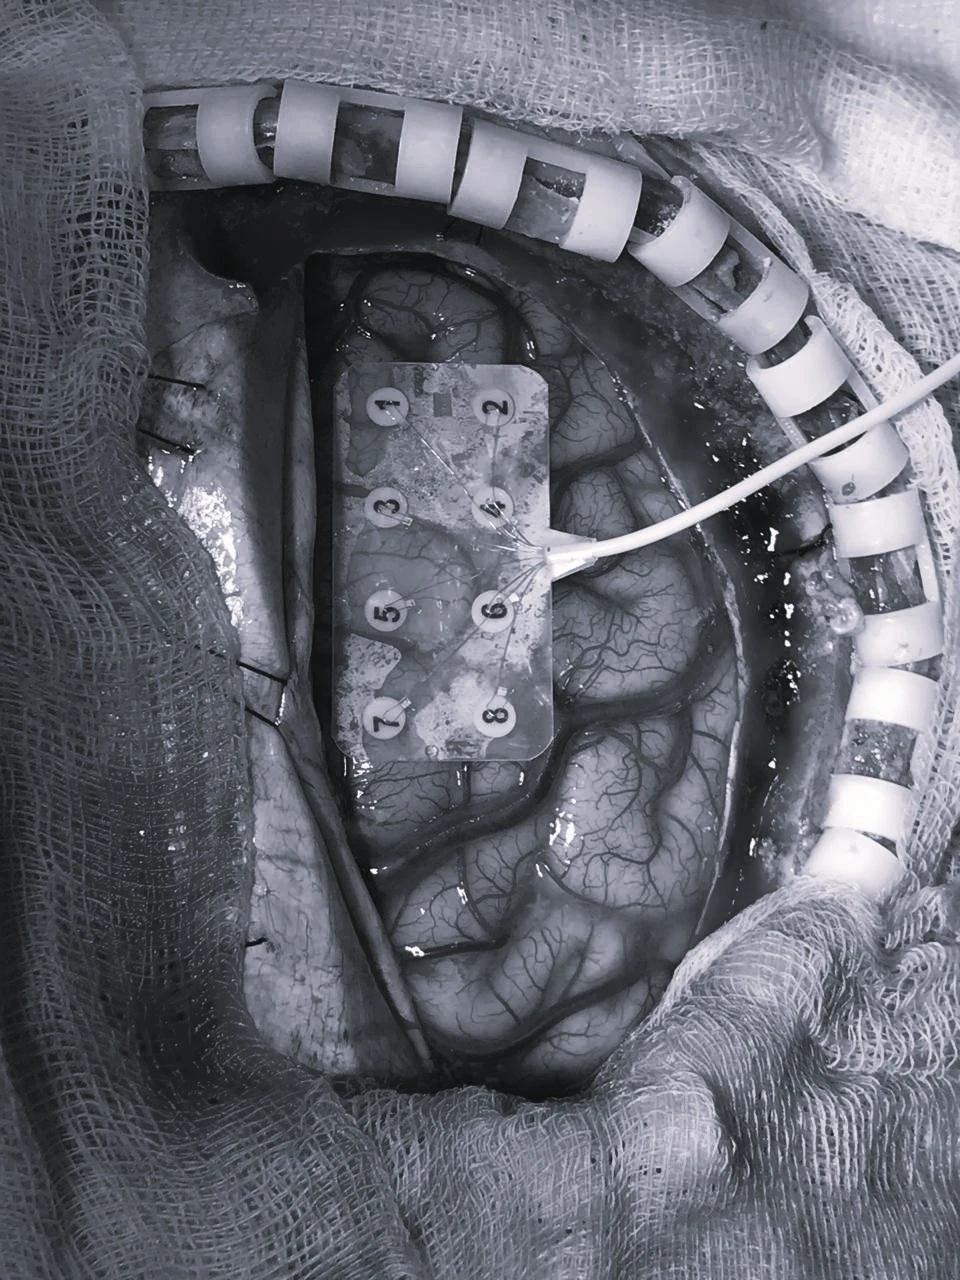

Operación en el Instituto Nacional de Ciencias Neurológicas

Cirugía Cerebral Avanzada

Innovación en Neurocirugía en Perú

Con más de 15 años transformando vidas, el Dr. Carlos Mao Tse Tung Vásquez Pérez lidera la neurocirugía en Perú. Su enfoque en procedimientos avanzados, como la cirugía funcional y oncológica, redefine el estándar de atención médica. Cada intervención no solo es un desafío superado, sino una historia de esperanza y resultados excepcionales.